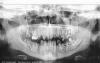

ден Опубликовано 10 октября, 2012 Поделиться Опубликовано 10 октября, 2012 Здравствуйте уважаемые коллеги. Помогите пожалуйста советом.Опыт имплантации небольшой,но есть.Несколько лет работал в клинике самостоятельно, с ортопедом находили общий язык и расхождений в плане лечения не было.Недавно устроился на другую работу. В этой клинике ортопед авторитетный и все с ним считаются.Хотя и сами у него не протезируются, потому как осложнений много и переделок.Но авторитет свой, доктор сохраняет.Так вот к сути вопроса, пришёл пациент 28 лет.Говорит что у него было тяжёлое финансовое положение, в течении нескольких лет. Теперь трудности позади и на новой должности он должен улыбаться и быть красивым.Денежный вопрос его интересует, но не особо.Заболеваний нет.Правда навыки гигиены "хромают".Есть несколько свищевых ходов. Так же отмечается хронический пародонтит с явлениями резорбции костной ткани во фронтальном отделе нижней челюсти. Вот что имеем.Ничего не беспокоит,кроме эстетики. Это тот план который я предложил.После удаления где то потребуется внесение в лунку остеотропа. После удаления всех зубов можно одеть временно съёмный протез. Сам я не протезирую, поэтому обратился к ортопеду,он мой план раскритиковал и предложил свой Мотивируя тем что для удаления показаний нет,и всё что можно "спасти" надо "спасать". Депульпировать и покрывать коронками. Причём мой довод о том что мы удаляем подросткам здоровые премоляры для нормализации прикуса не возимели действие.И тот же парадонтит, подвижность 2 степени и гноетечение, не остудил его академический пыл.Подскажите пожалуйста, как бы Вы поступили в данной ситуации? Хочется чтоб "не навреди"... Ссылка на комментарий

Bier Опубликовано 10 октября, 2012 Поделиться Опубликовано 10 октября, 2012 мне категорически не нравятся оба плана лечения. Ну план вашего ортопеда даже обсуждать не хочу, он мягко говоря странный.Теперь про ваш план:верх - согласен с тотальным удалением (но не сразу) не нравится:1. расположение имплантатов (ставить 2 имплантата в резцы нет никакого смысла, на нижней челюсти даже вредно. Я бы вообще очень задумался над тем, нужны ли вообще имплантаты в резцах (внизу точно не нужны), а наверху максимум 1.2. Вы собираетесь в лунки имплантировать? У пациента 13 зуб мезиализирован. Имплантат в этой позиции нам не нужен. При моделировке коронок он окажется между зубов. 47з - вы специально выбрали место с самой большой гранулемой? ))3. Ношение съемных протезов с опорой на слизистую на мой взгляд недопустимо вообще в такой ситуации. Надо искать способы обойтись без них. не удалять сразу все зубы, а оставить часть зубов для фиксации протеза, установить часть имплантатов, после их приживления удалить оставшиеся зубы и доимплантироваться. На нижней челюсти фронтальная группа не выглядит криминальной. Полечите пародонтит, какие проблемы? И гноетечение пройдет и зубы еще постоят. 2 Ссылка на комментарий

pawa Опубликовано 10 октября, 2012 Поделиться Опубликовано 10 октября, 2012 не удалять сразу все зубы, а оставить часть зубов для фиксации протеза, установить часть имплантатов, после их приживления удалить оставшиеся зубы и доимплантироваться. Вот это очень правильная мысль.Сейчас стараюсь при любой возможности сохранять даже подвижные зубы для фиксации времянок на время интеграции. Обычно жто клыки, иногда ещё пятёрки.Но даже на двых клыках стоит подкова на 10 единиц! Главное высота коинич. коронок и суперклей)Пол года стоит без проблем. потом удаляются остатки и сразу нагружаются ранее установленные винты. Пац с зубами, МАВ сохранена, док с деньгами, все довольны) 1 Ссылка на комментарий